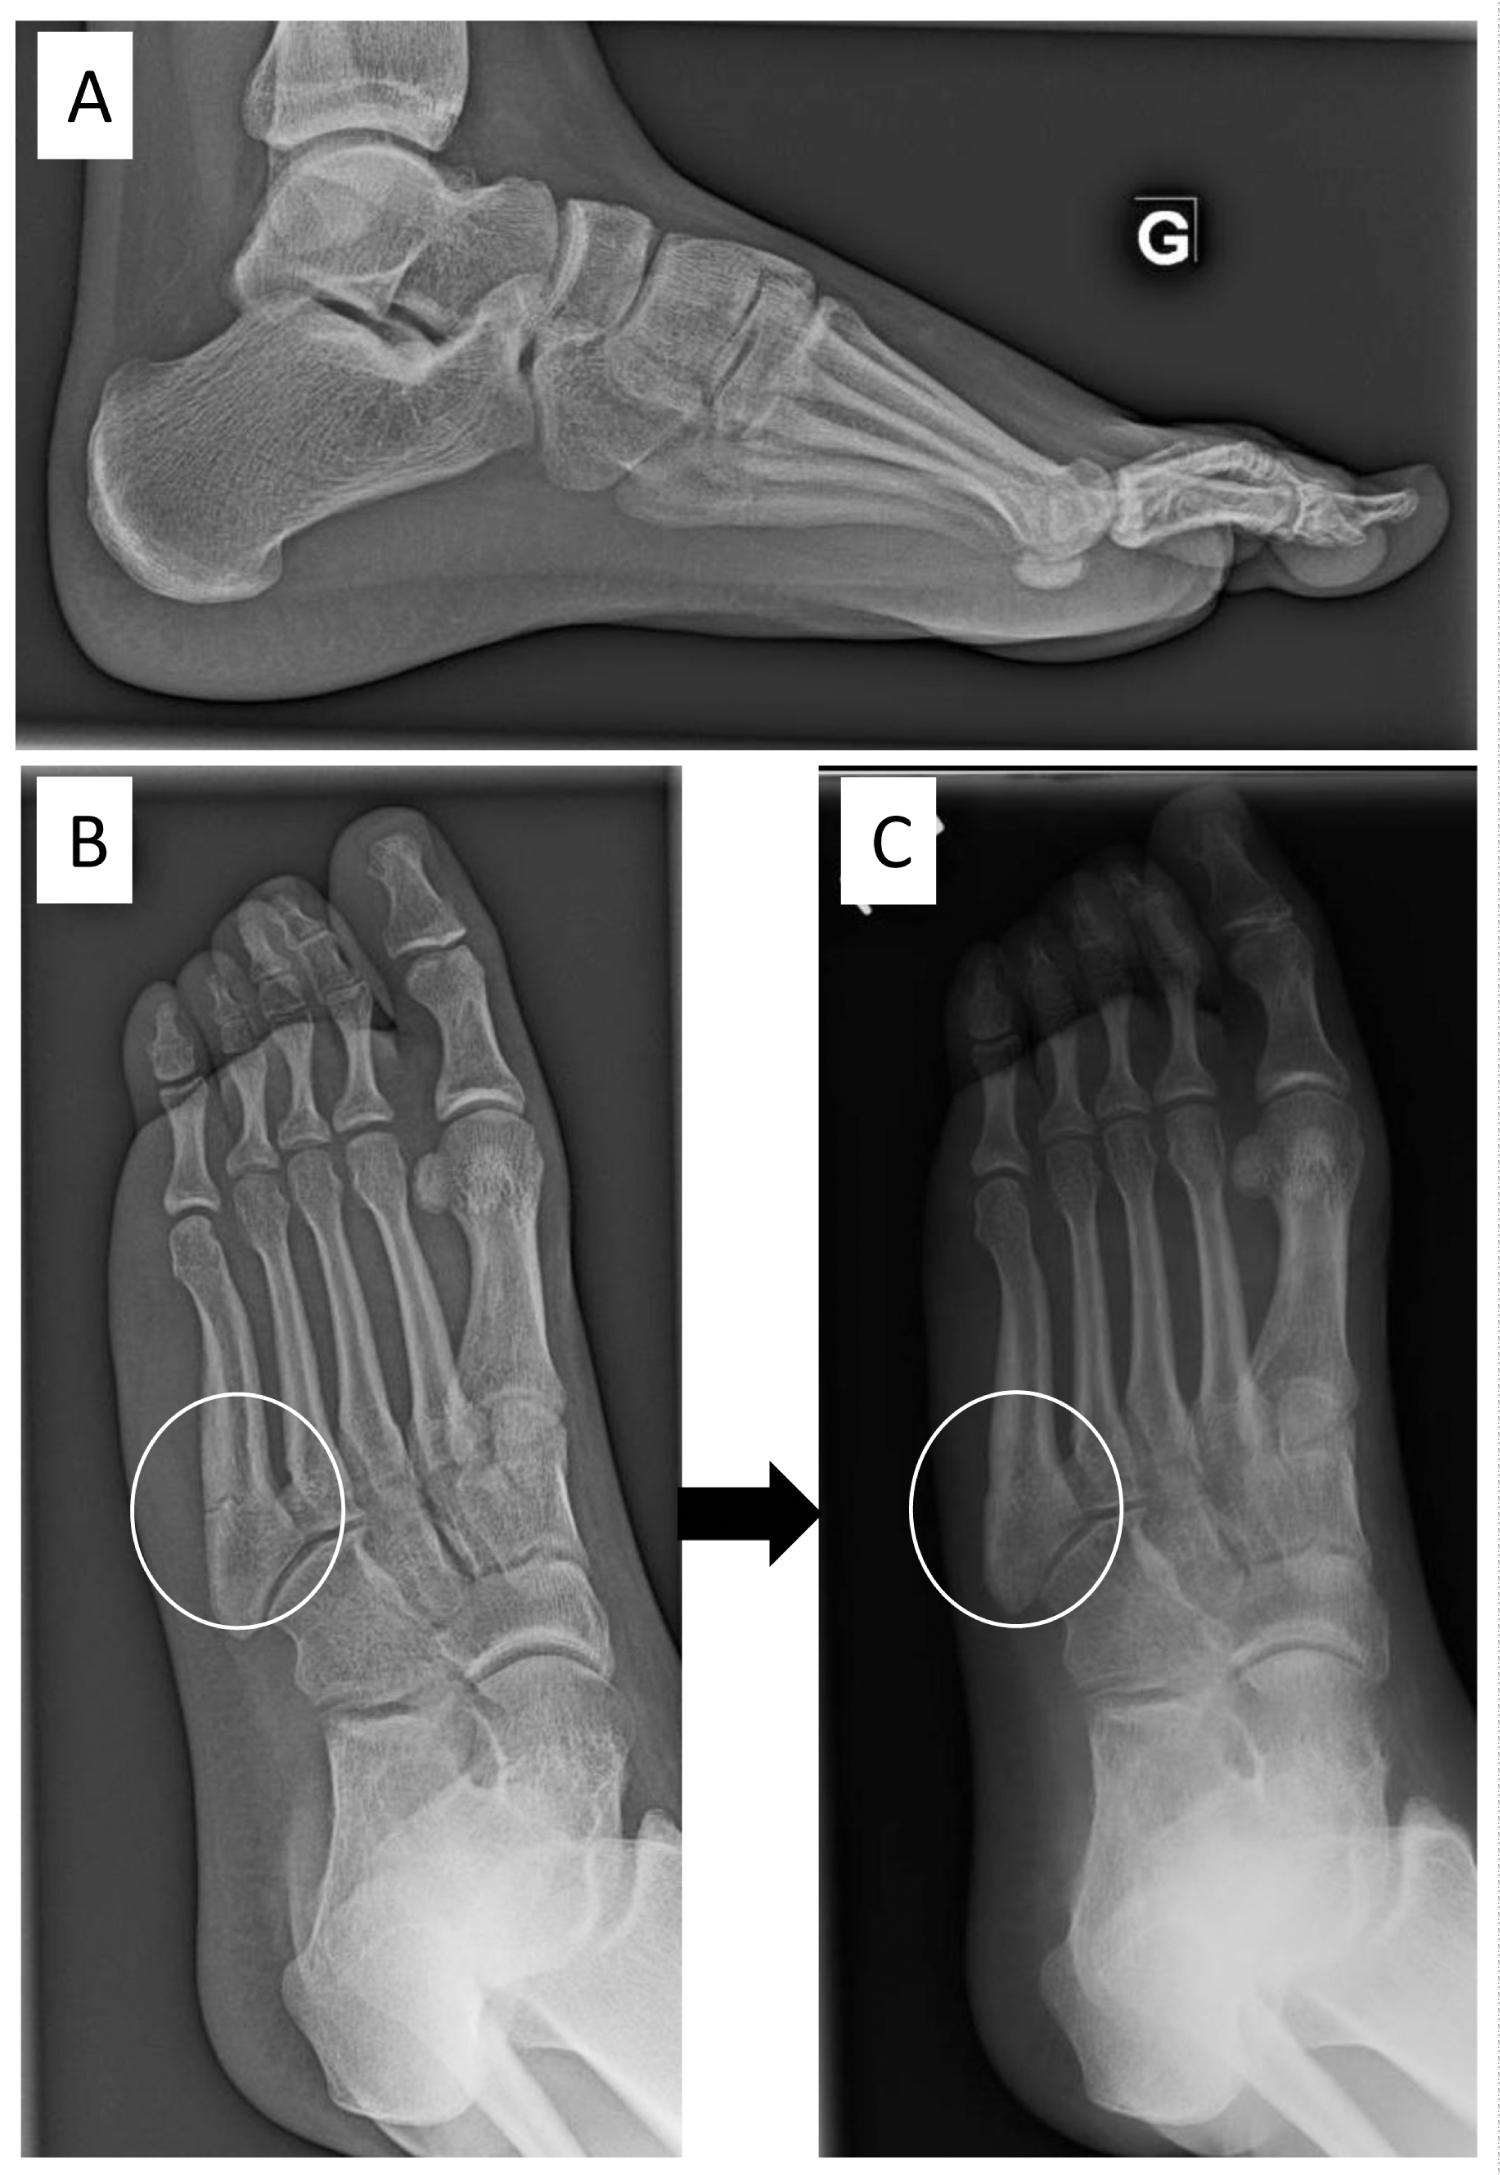

Figure 8: A 16-year-old female soccer player with a fracture of the 5th metatarsal in her left foot. She was treated with a non-weight bearing cast for 2 months, and progressively returned to sport. The same month, she fractured her 5th metatarsal bone (A, B). She wore a cast again and slowly healed. After 3-months, her subtle cavovarus foot was corrected with an insole. (C) After 6 months, she was clinically asymptomatic, returned to soccer with an insole and did not re-fracture. View Figure 8